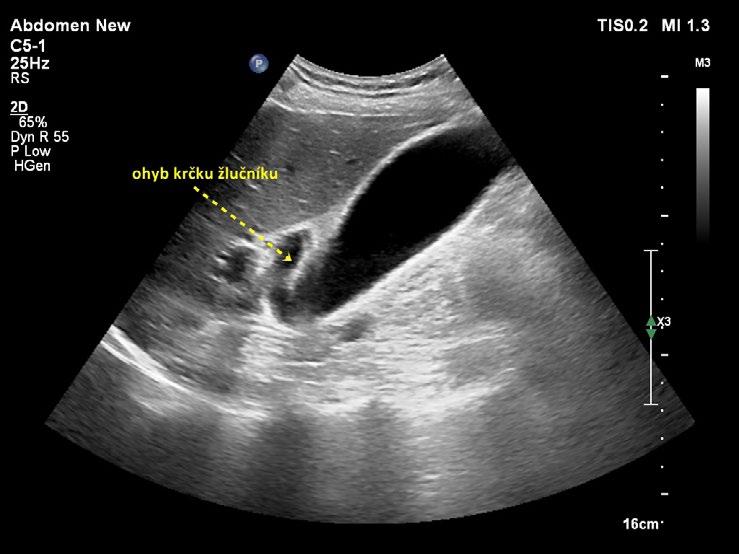

Žlučník prohlížíme v celém rozsahu (krček, infundibulum, tělo a fundus), v dlouhé a krátké ose a ve více rovinách zobrazení. V krčku lze příležitostně zobrazit spirální slizniční řasu (Heisterovu chlopeň). Za spirální řasou vzniká dorzální akustický stín, který může vést k mylné diagnóze konkrementu v krčku žlučníku. Krček a infundibulum žlučníku mají vztah k hilu jater a jsou místy, kde hledáme případný zaklíněný konkrement při akutní cholecystitidě. Fundus je uložen pod spodní plochou jater a přibližuje se k přední břišní stěně nejčastěji v medioklavikulární čáře, jeho uložení je však značně variabilní – od levé subhepatické oblasti až do pravé prerenální pozice (obr. 1.3). Fundus je místem, kde dochází nejčastěji k perforaci žlučníku při akutní komplikované cholecystitidě.

Kromě běžného kapkovitého tvaru mívá žlučník řadu tvarových variací. Časté je zahnutí žlučníku v oblasti krčku (obr. 1.4), těla (obr. 1.5) nebo fundu. Zahnutí bývá mnohdy i několikanásobné (obr. 1.6) a může v některých rovinách zobrazení vytvářet falešný dojem septace (obr. 1.7). Skutečné septum žlučníku je ale vzácné (0,02 % pitevních nálezů). Nalézá se například při duplikatuře žlučníku, při které je lumen rozděleno podélným septem a každá z polovin žlučníku je drénována vlastním ductus cysticus. Ohyb v infundibulu a krčku může imitovat dilataci hepatocholedochu (obr. 1.8). Při nízce odstupujícím ductus cysticus se ohyb krčku žlučníku může sumovat s hlavou pankreatu a vytvářet mylný dojem dilatace intrapankreatické části hepatocholedochu. Pečlivé vyšetření hlavy pankreatu a celého průběhu hepatocholedochu ve vícero zobrazovacích rovinách vede k odlišení ohybu žlučníku od vlastního nedilatovaného intrapankreatického hepatocholedochu (obr. 1.9).